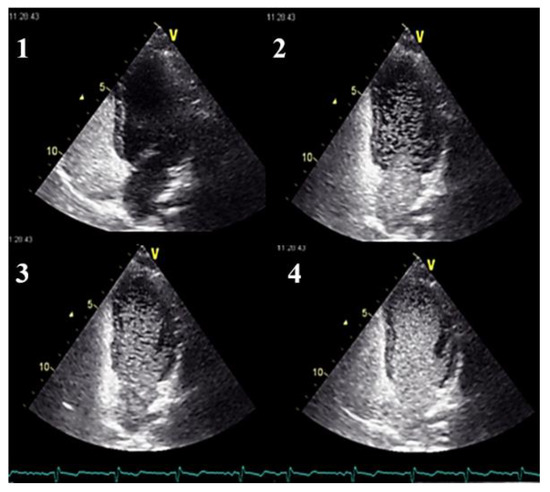

- Clinicians should use transthoracic contrast echocardiography as the initial screening test for pulmonary AVMs.